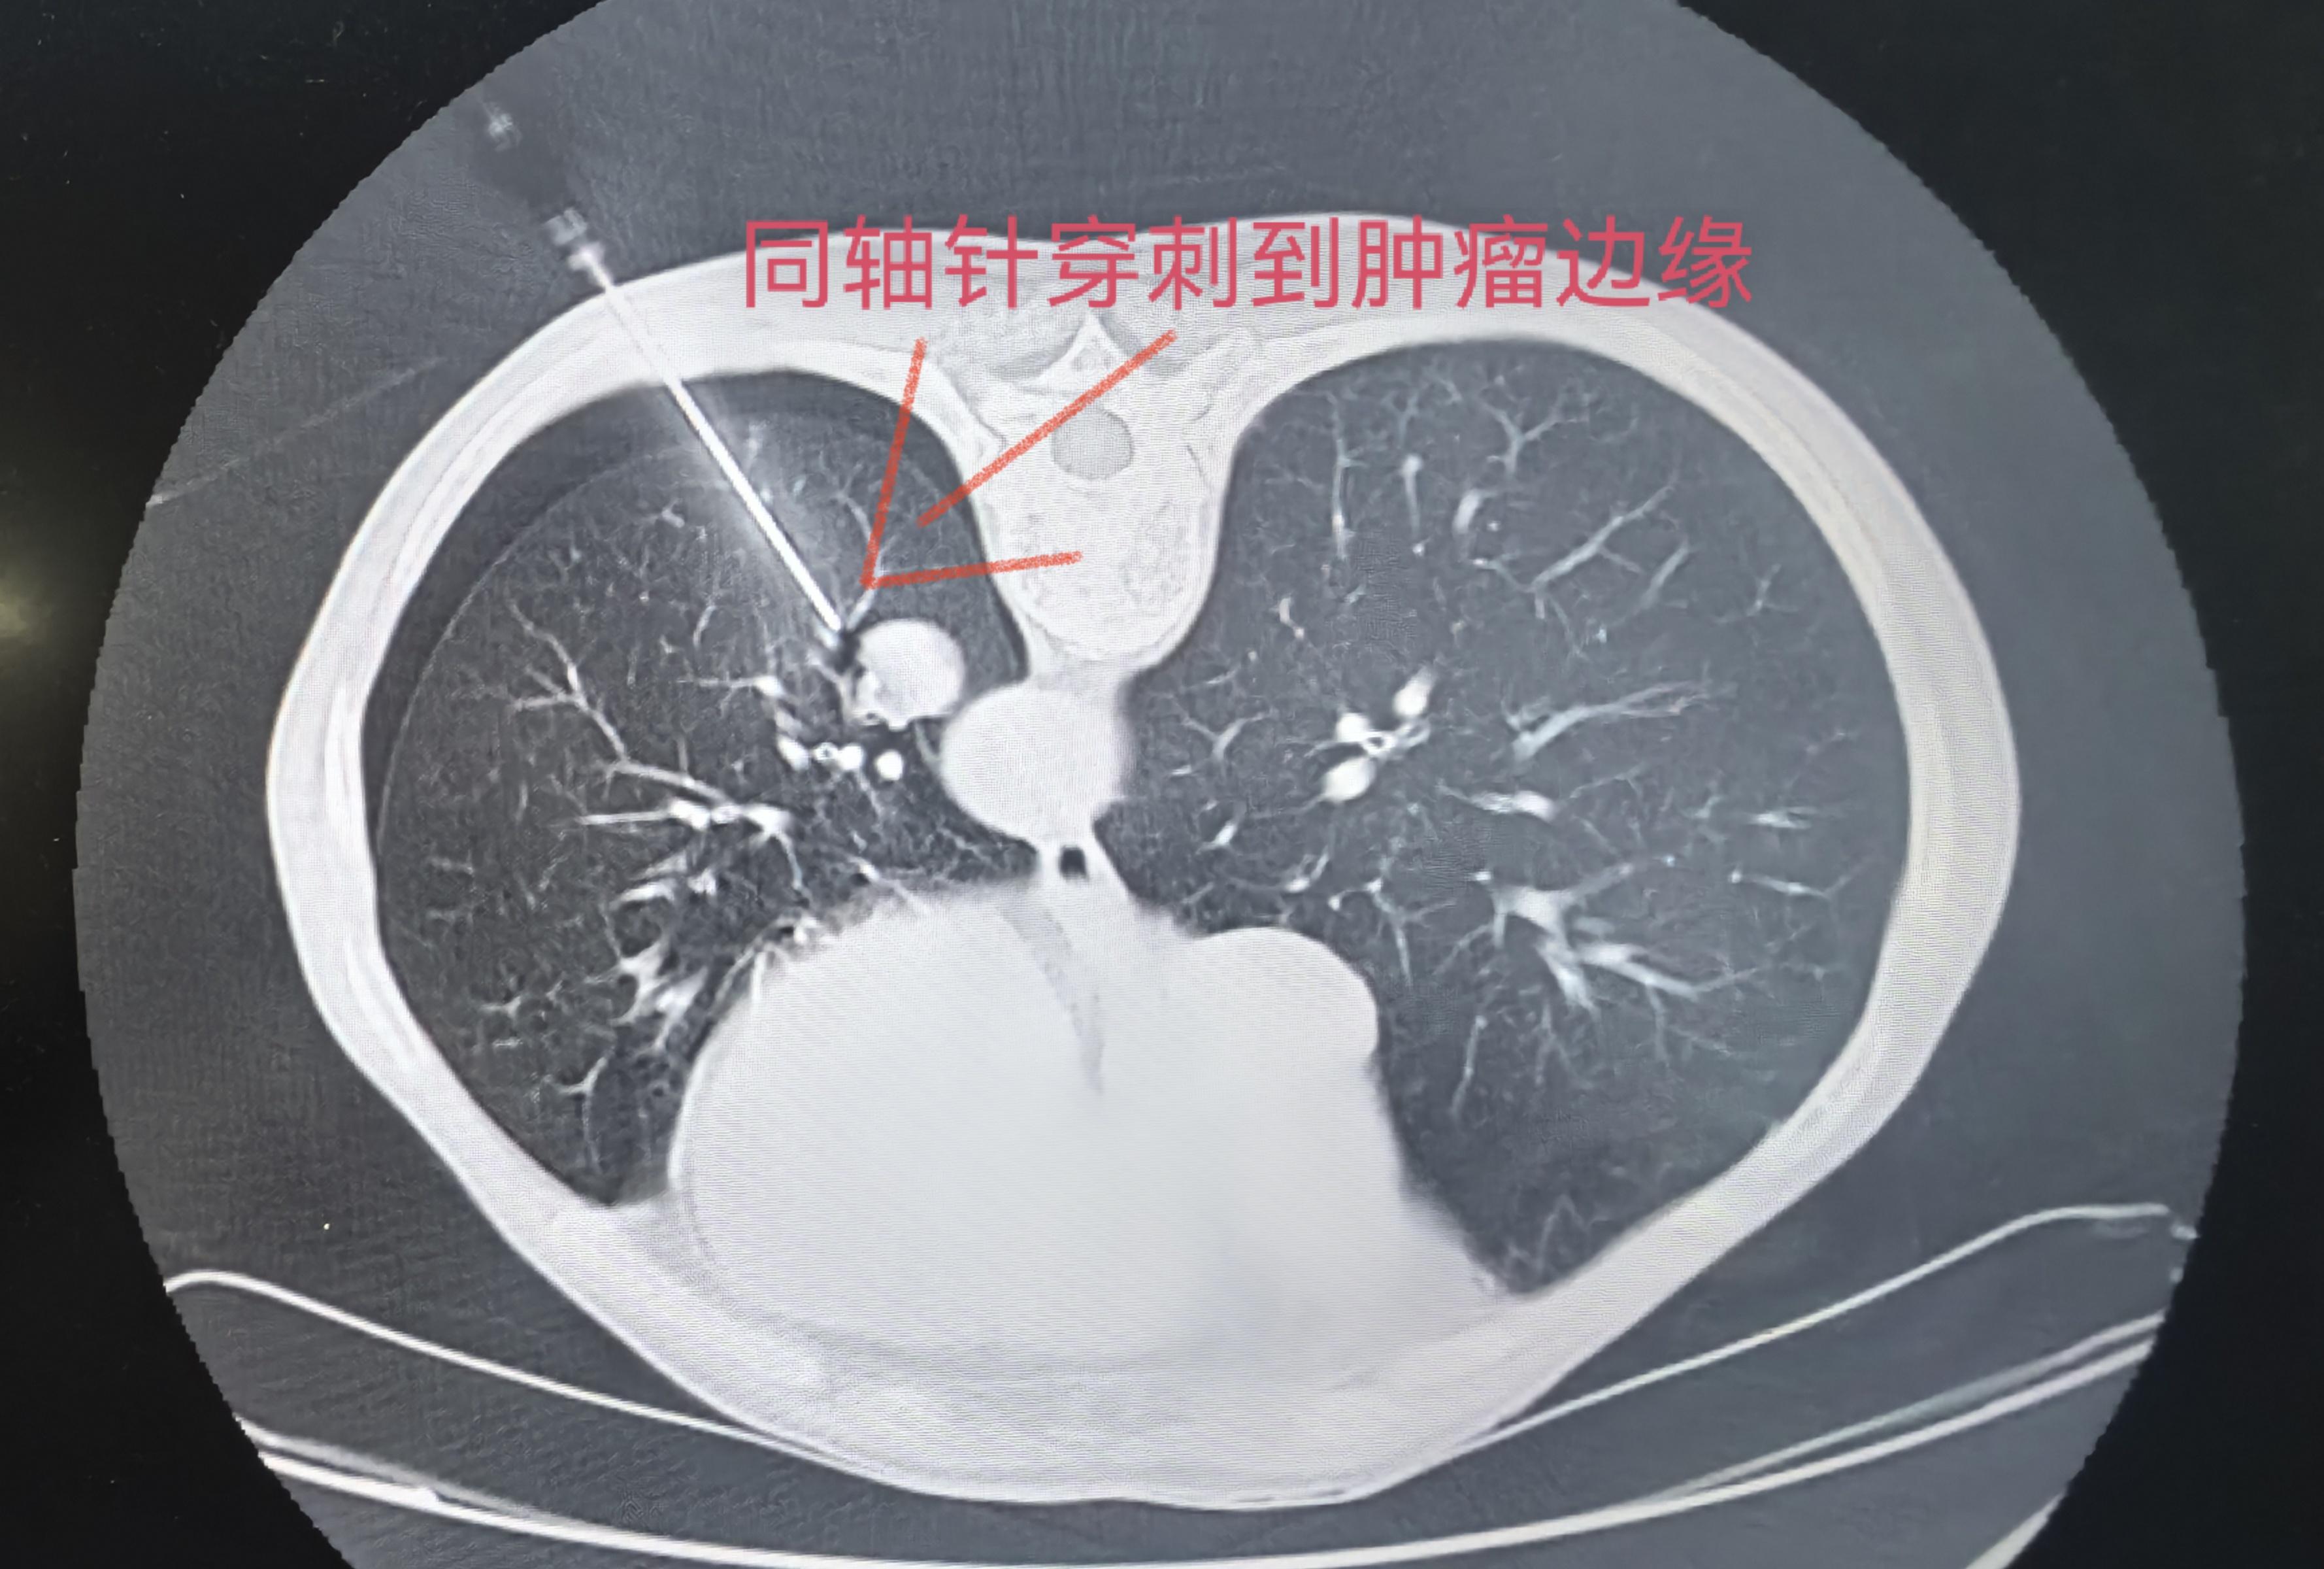

CT引导下实体肿块经皮刺活检术,精准穿刺。CT引导下实体肿块经皮刺活检...

第一台右肺下叶结节穿刺活检!

第二台气管旁占位及胸椎旁占位同步第到活检!

第一台右肺下叶结节穿刺活检! 第二台气管旁占位及胸椎旁占位同步第到活检!